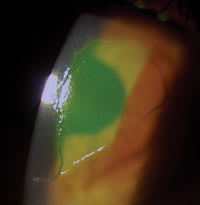

| Figure 1: Corneal abrasion at first visit. |

An established patient reported to the office with corneal trauma. Two days prior, the patient had an accident in which soap squirted on to the front surface of the right eye. He reported considerable pain, decreased vision and photophobia, none of which were improving. We diagnosed the patient with a large corneal abrasion (see figure 1).

We coded the initial visit with the appropriate level evaluation and management visit code, 99213 in this case, and code 92070 for the fitting and supply of the bandage lens, as well as code 99285 for anterior segment photography. The diagnosis codes for this example were corneal abrasion (918.1) and secondary iritis (364.04). The patient had several follow-up visits where we assessed corneal health with biomicroscopy and high mol-ecular weight fluourescein through the lens, but did not remove the bandage lens (see figure 2).